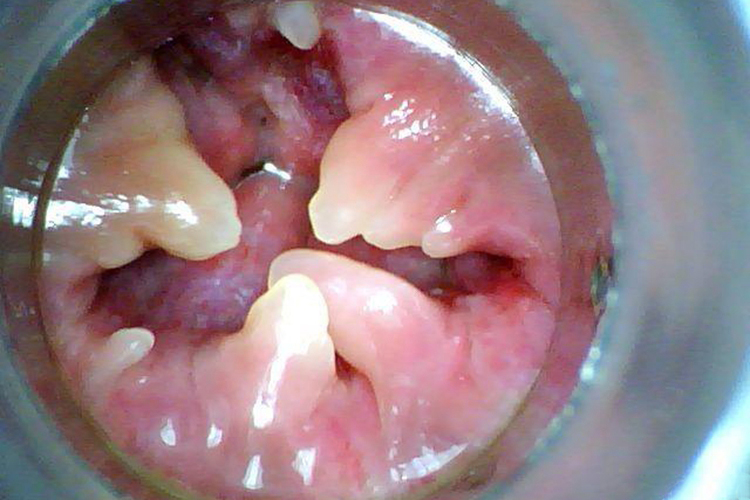

主要表现为平时感到肛门内有异物感,随着肛乳头增生肥大,排便时肛乳头可脱出肛门外。小的肛乳头便后可自行回到肛门内,大的需用手推回肛门内。肛乳头肥大生于齿状线部,系肛管上皮组织增生,乳白色,质硬,不易出血。

肛乳头长到一定程度,大便时能脱出肛外。开始大便后能自行回缩于肛内,逐渐需用手推方能缩回肛内,甚至长期脱出肛外。肥大肛乳头脱出肛门外后,如果未及时推回肛内,则会发生嵌顿,嵌顿后,水肿、疼痛均剧烈,行动不便,坐卧不宁,甚至大小便均困难。